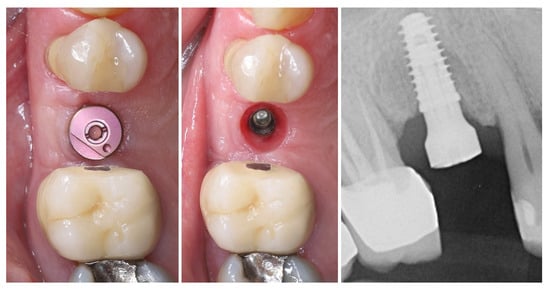

The implant was placed using a digitally designed surgical guide to ensure prosthetically driven positioning. Intraoperative images demonstrate the sequence of guided placement: preparation of the osteotomy through the guide with visualization of the prepared site (left), dental implant (T3Pro, ZimVie Inc., Palm Beach Gardens, FL, USA) before placement (middle), and final implant insertion (right) with insertion torque ~50N/cm. The use of a surgical template allowed precise three-dimensional implant placement, optimal angulation, and preservation of surrounding soft and hard tissues (Figure 8).

Figure 8.

Guided implantation protocol.

The selected implant was positioned in the prosthetically driven position, with appropriate bone thickness at the buccal aspect and surrounded by healthy soft tissues (left). Another advantage of this surgical approach is the possibility to adapt the implant insertion depth corresponding to the soft tissue thickness in order to provide enough soft tissue thickness to enhance the stability of the peri-implant bone. The intraoperative measurements confirmed excellent primary stability, with ISQ values of 82 bucco-lingually and 85 mesio-distally (right). These parameters indicated optimal mechanical anchorage of the fixture within the alveolar bone, ensuring favourable conditions for osseointegration (Figure 9).

Figure 9.

Implant placement and initial stability.

A multi-purpose healing abutment, serving also as a scan body (encode abutment ZimVie Inc., Palm Beach Gardens, FL, USA), was connected, providing proper concave emergence profile in the critical contour zone of the transmucosal area. The de-epithelized crestal flap was rolled and fixated to the inner surface of the buccal flap with a horizontal mattress suture (7/0 PGA). The buccal flap was fixed to the “anatomical” part of the peri-implant papillae (6/0 PGA). The buccal positioning of the rolled connective tissue creates a thickened gingival margin, intended to improve peri-implant soft tissue stability and long-term esthetic outcomes. The surgical site shows adequate adaptation of the flap margins around the healing abutment, enhancing the primary healing, thus reflecting proper flap management and atraumatic technique. The 2D X-ray performed after implant placement shows a proper implant position corresponding to the morphology of the alveolar crest (Figure 10).

Figure 10.

Clinical and X-ray view after implant placement and roll flap adaptation.